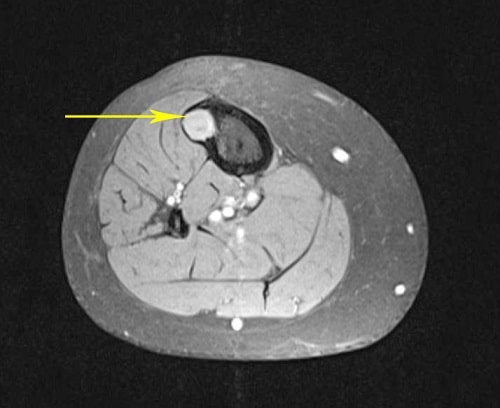

OFD in tibia

In this cross-section CT scan of the tibia, an OFD shows up clearly as bright white against the darker color of the bone.